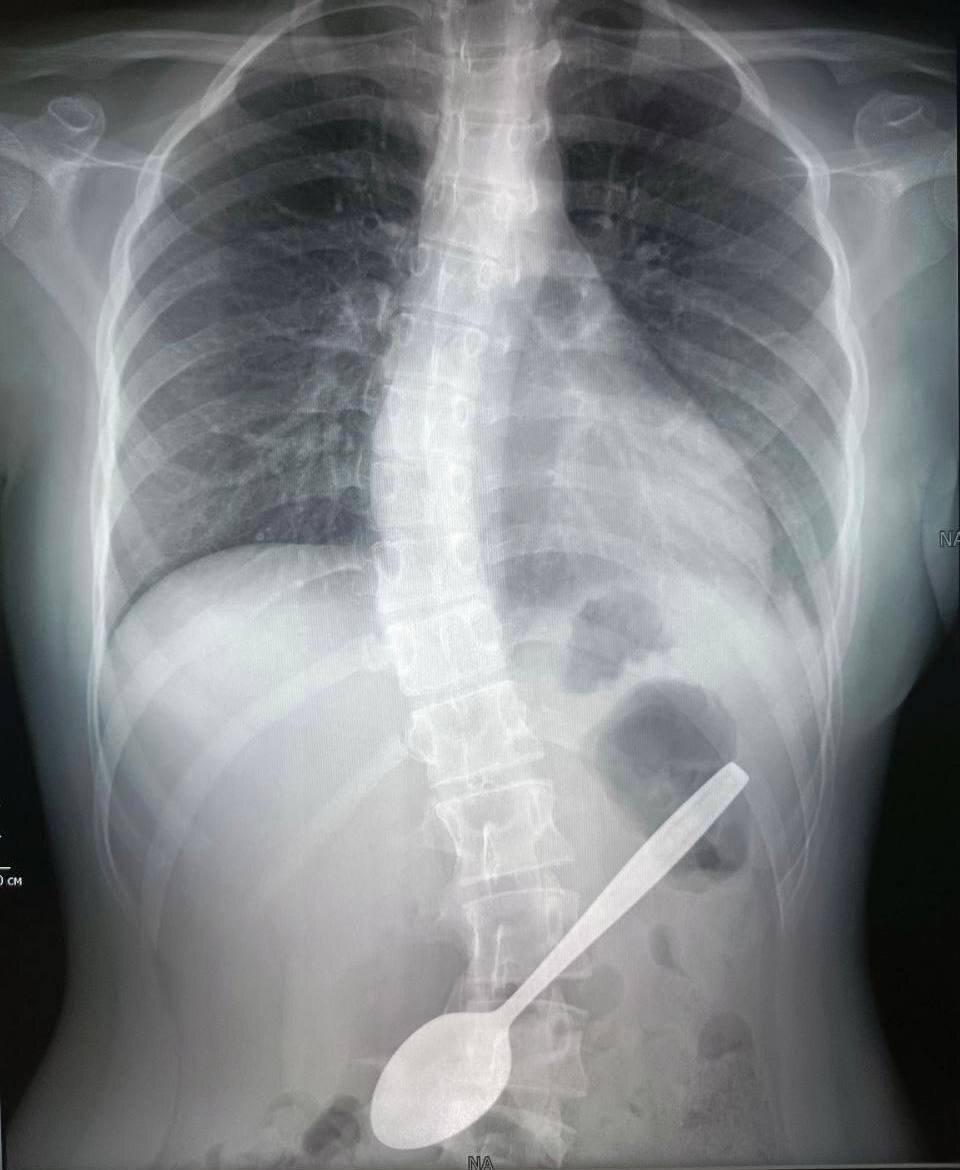

πŸ˜±Π¨ΠΊΠΎΠ»ΡŒΠ½ΠΈΡ†Π° ΠΈΠ· Подмосковья ΠΏΡ€ΠΎΠ³Π»ΠΎΡ‚ΠΈΠ»Π° 15-ΡΠ°Π½Ρ‚ΠΈΠΌΠ΅Ρ‚Ρ€ΠΎΠ²ΡƒΡŽ Π»ΠΎΠΆΠΊΡƒ Π² ΠΏΠΎΠΏΡ‹Ρ‚ΠΊΠ΅ Π΄ΠΎΡΡ‚Π°Ρ‚ΡŒ Сю кусок яблока, ΠΊΠΎΡ‚ΠΎΡ€Ρ‹ΠΉ застрял Ρƒ Π½Π΅Π΅ Π² Π³ΠΎΡ€Π»Π΅ 14-Π»Π΅Ρ‚Π½ΡŽΡŽ Π΄Π΅Π²ΠΎΡ‡ΠΊΡƒ доставили Π² Π±ΠΎΠ»ΡŒΠ½ΠΈΡ†Ρƒ, ΠΈ Ρ‚Π°ΠΌ ΡƒΠΆΠ΅ с ΠΏΠΎΠΌΠΎΡ‰ΡŒΡŽ хирургичСского Π·Π°ΠΆΠΈΠΌΠ° ΠΈ эндоскопа ΠΈΠ·Π²Π»Π΅ΠΊΠ»ΠΈ ΠΈΠ½ΠΎΡ€ΠΎΠ΄Π½Ρ‹ΠΉ ΠΏΡ€Π΅Π΄ΠΌΠ΅Ρ‚. БСйчас ΠΎΠ½Π° чувствуСт сСбя Ρ…ΠΎΡ€ΠΎΡˆΠΎ ΠΈ ΡƒΠΆΠ΅ выписана Π΄ΠΎΠΌΠΎΠΉ.

14-Π»Π΅Ρ‚Π½ΡŽΡŽ Π΄Π΅Π²ΠΎΡ‡ΠΊΡƒ доставили Π² Π±ΠΎΠ»ΡŒΠ½ΠΈΡ†Ρƒ, ΠΈ Ρ‚Π°ΠΌ ΡƒΠΆΠ΅ с ΠΏΠΎΠΌΠΎΡ‰ΡŒΡŽ хирургичСского Π·Π°ΠΆΠΈΠΌΠ° ΠΈ эндоскопа ΠΈΠ·Π²Π»Π΅ΠΊΠ»ΠΈ ΠΈΠ½ΠΎΡ€ΠΎΠ΄Π½Ρ‹ΠΉ ΠΏΡ€Π΅Π΄ΠΌΠ΅Ρ‚. БСйчас ΠΎΠ½Π° чувствуСт сСбя Ρ…ΠΎΡ€ΠΎΡˆΠΎ ΠΈ ΡƒΠΆΠ΅ выписана Π΄ΠΎΠΌΠΎΠΉ.